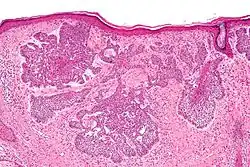

Nodular basal-cell carcinoma

.jpg)

Nodular basal-cell carcinoma (also known as "classic basal-cell carcinoma") accounts for 50% of all BCC.[29] It most commonly occurs on the sun-exposed areas of the head and neck.[30]: 748 [31]: 646 Histopathology shows aggregates of basaloid cells with well-defined borders, showing a peripheral palisading of cells and one or more typical clefts.[29] Such clefts are caused by shrinkage of mucin during tissue fixation and staining.[32] Central necrosis with eosinophilic, granular features may also be present, as well as mucin. The heavy aggregates of mucin determine a cystic structure. Calcification may also be present, especially in long-standing lesions.[29] Mitotic activity is usually not so evident, but a high mitotic rate may be present in more aggressive lesions.[29] Adenoidal BCC can be classified as a variant of NBCC, characterized by basaloid cells with a reticulated configuration extending into the dermis.[29]